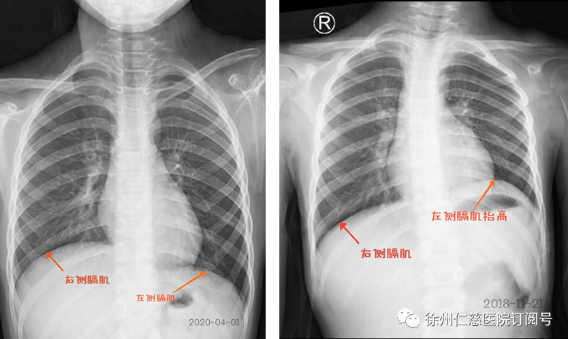

2020年4月,伤后一年半,甜甜的肩关节外展、肘关节屈曲都比之前有力了,肩肘活动度均已接近正常水平,拍胸片显示,左侧膈肌降下来了,说明膈神经也已经恢复。甜甜的妈妈特别高兴,十分感激陈主任的救治,她说不但自己担心孩子恢复得不好,甜甜也经常小声地问她:“妈妈,我什么时候才能好啊?”陈主任感慨道:“小姑娘很勇敢,比成年人所承受的疼痛和辛苦更多,现在神经恢复了,她的心结也打开了!”一年多以来闷闷不乐的甜甜终于露出了灿烂的笑容。

胸部平片